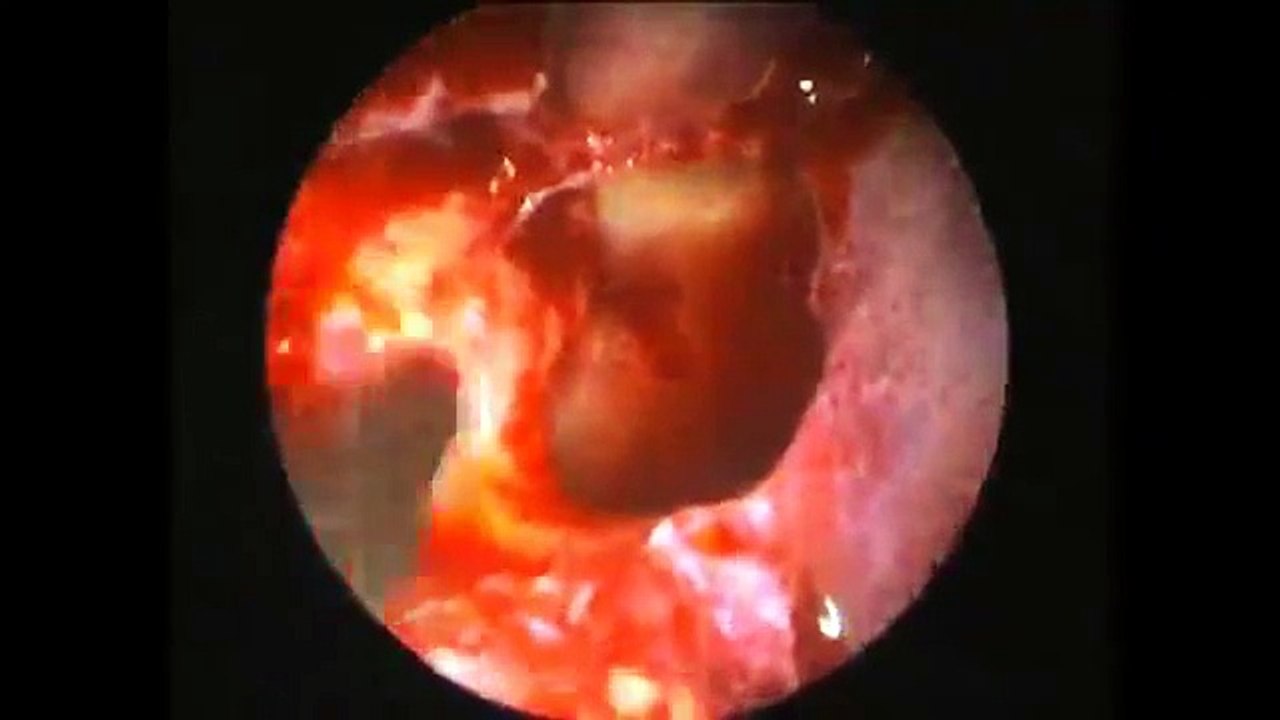

Pachymeningitis

Pachymeningitis - http://goo.gl/4w4Gf9